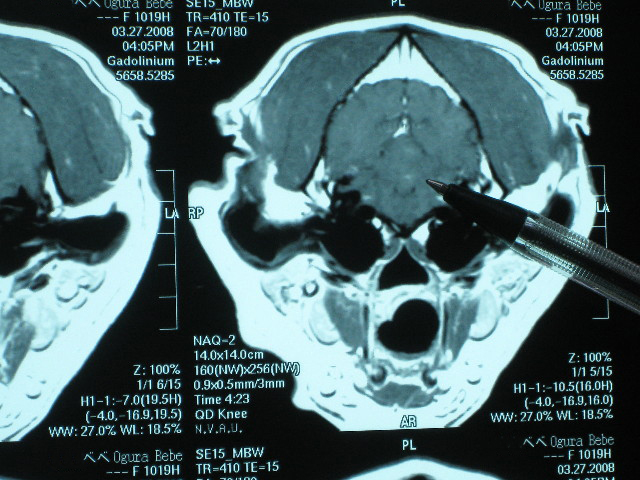

他の断面からみた小脳梗塞病変箇所。

こんな小さなポチで、こんなに大変な事になっちゃうんだよね....。

MRIのフィルムはね、お願いすると有料で現像してくれるの。

先生に診ていただくために全4枚を現像してもらってもらって帰ってきたんだよ。

ロールシャッハテストの絵みたいだよね。